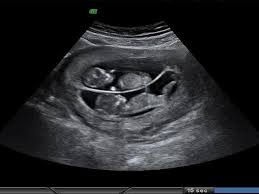

Ось я заходжу,лягаю....і просто починаю тихенько плакати поки лікар оглядає живіт....він так довго водив датчиком,що мені здалось вічність пройшла...він щось водив,зводив брови ,дивився на мене і знову водив....

Він знову звів свої брови,нахмурився і каже...то ви ще незнаєте ,що у вас тут...ДВОПОВЕРХОВА КВАРТИРА!

І він повертає до мене екран і каже...слухайте...і включає серцебиття одне,а потім знову серцебиття...ще одне ...я ще не можу зрозуміти і лише тоді коли він на екрані наводить датчик,щоб бачити двох діток зразу..до мене дійшло!Я почала плакати ще більше і просто його обняла,а він мене!

Він мабуть подумав що я якась дивна, а в той момент я просто була щаслива,що сердечко б'ється в мені і не одне.Цей звук...навіть минув рік,а я його згадую в пам'яті і досі...це звук ЩАСТЯ ,да і ще в такий тяжкий і складний період.